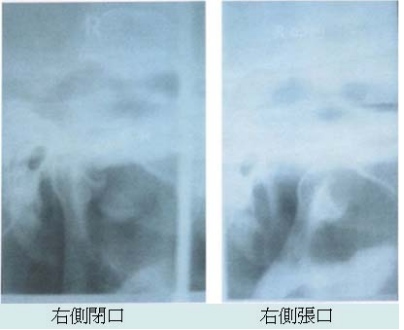

49. 右側穿顱式攝影可見下顎骨髁頭,從x-ray判讀,下列何者為較不可能之診斷?

(A)骨瘤 (B)骨頭增生 (C)退化性關節疾病 (D)軟骨瘤